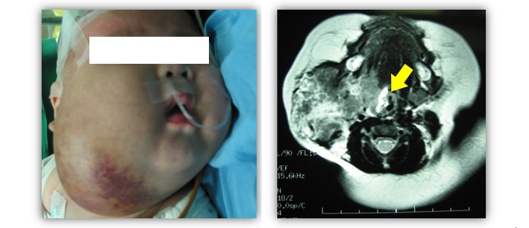

肩部巨大卡泼西样血管内皮瘤伴卡梅现象

图:下颌、颈部巨大卡泼西样血管内皮瘤伴卡梅现象,患儿伴有明显的气道压迫症状。